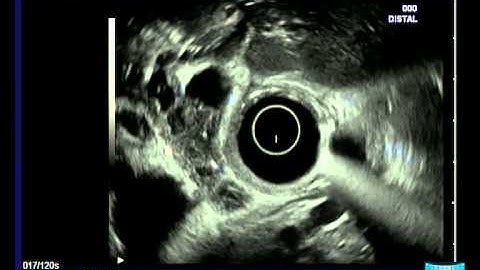

ENDOSCOPIC FEATURES OF THE HILAR CHOLANGIOCARCINOMA DURING CHOLANGIOSCOPY